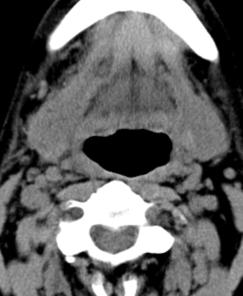

标题: CT17168:会诊,颈部包块 [打印本页]

标题: CT17168:会诊,颈部包块

怎么不传病史呢?右侧颌下腺炎症?

考虑:右侧颌下腺炎症。建议强化。

不排除右侧颌下腺恶性肿瘤可能;建议行进一步检查。

考虑:右侧颌下腺炎症可能。

我也是报的颌下腺炎症。